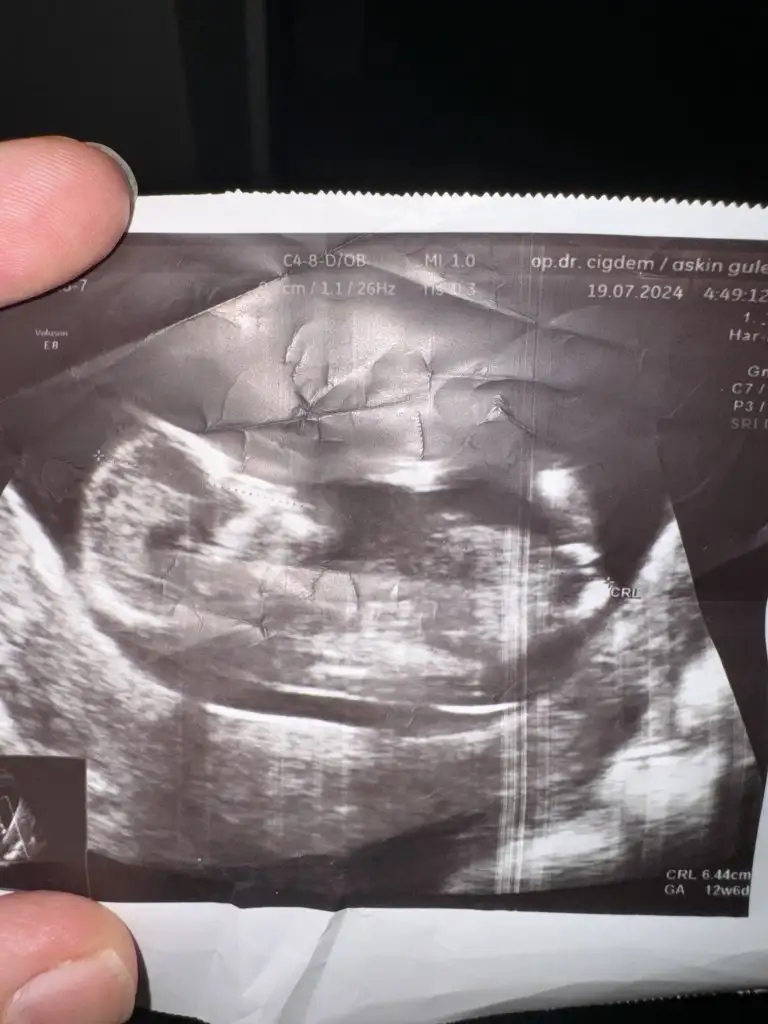

Merhaba arkadaşlar 12 haftalık hamileyiim doktor erkeğe benziyor dedi aranızda tahmin yapabilicek varmıı